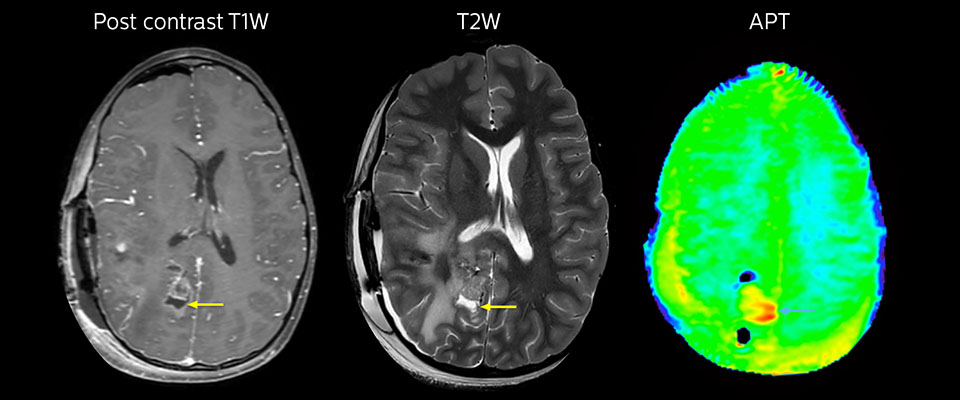

Tumor evaluation in a 1-year-old child with medulloblastoma. This aggressive tumor type is very solid and homogeneous. The high APT signal corresponds with the post-contrast image of this high-grade tumor.